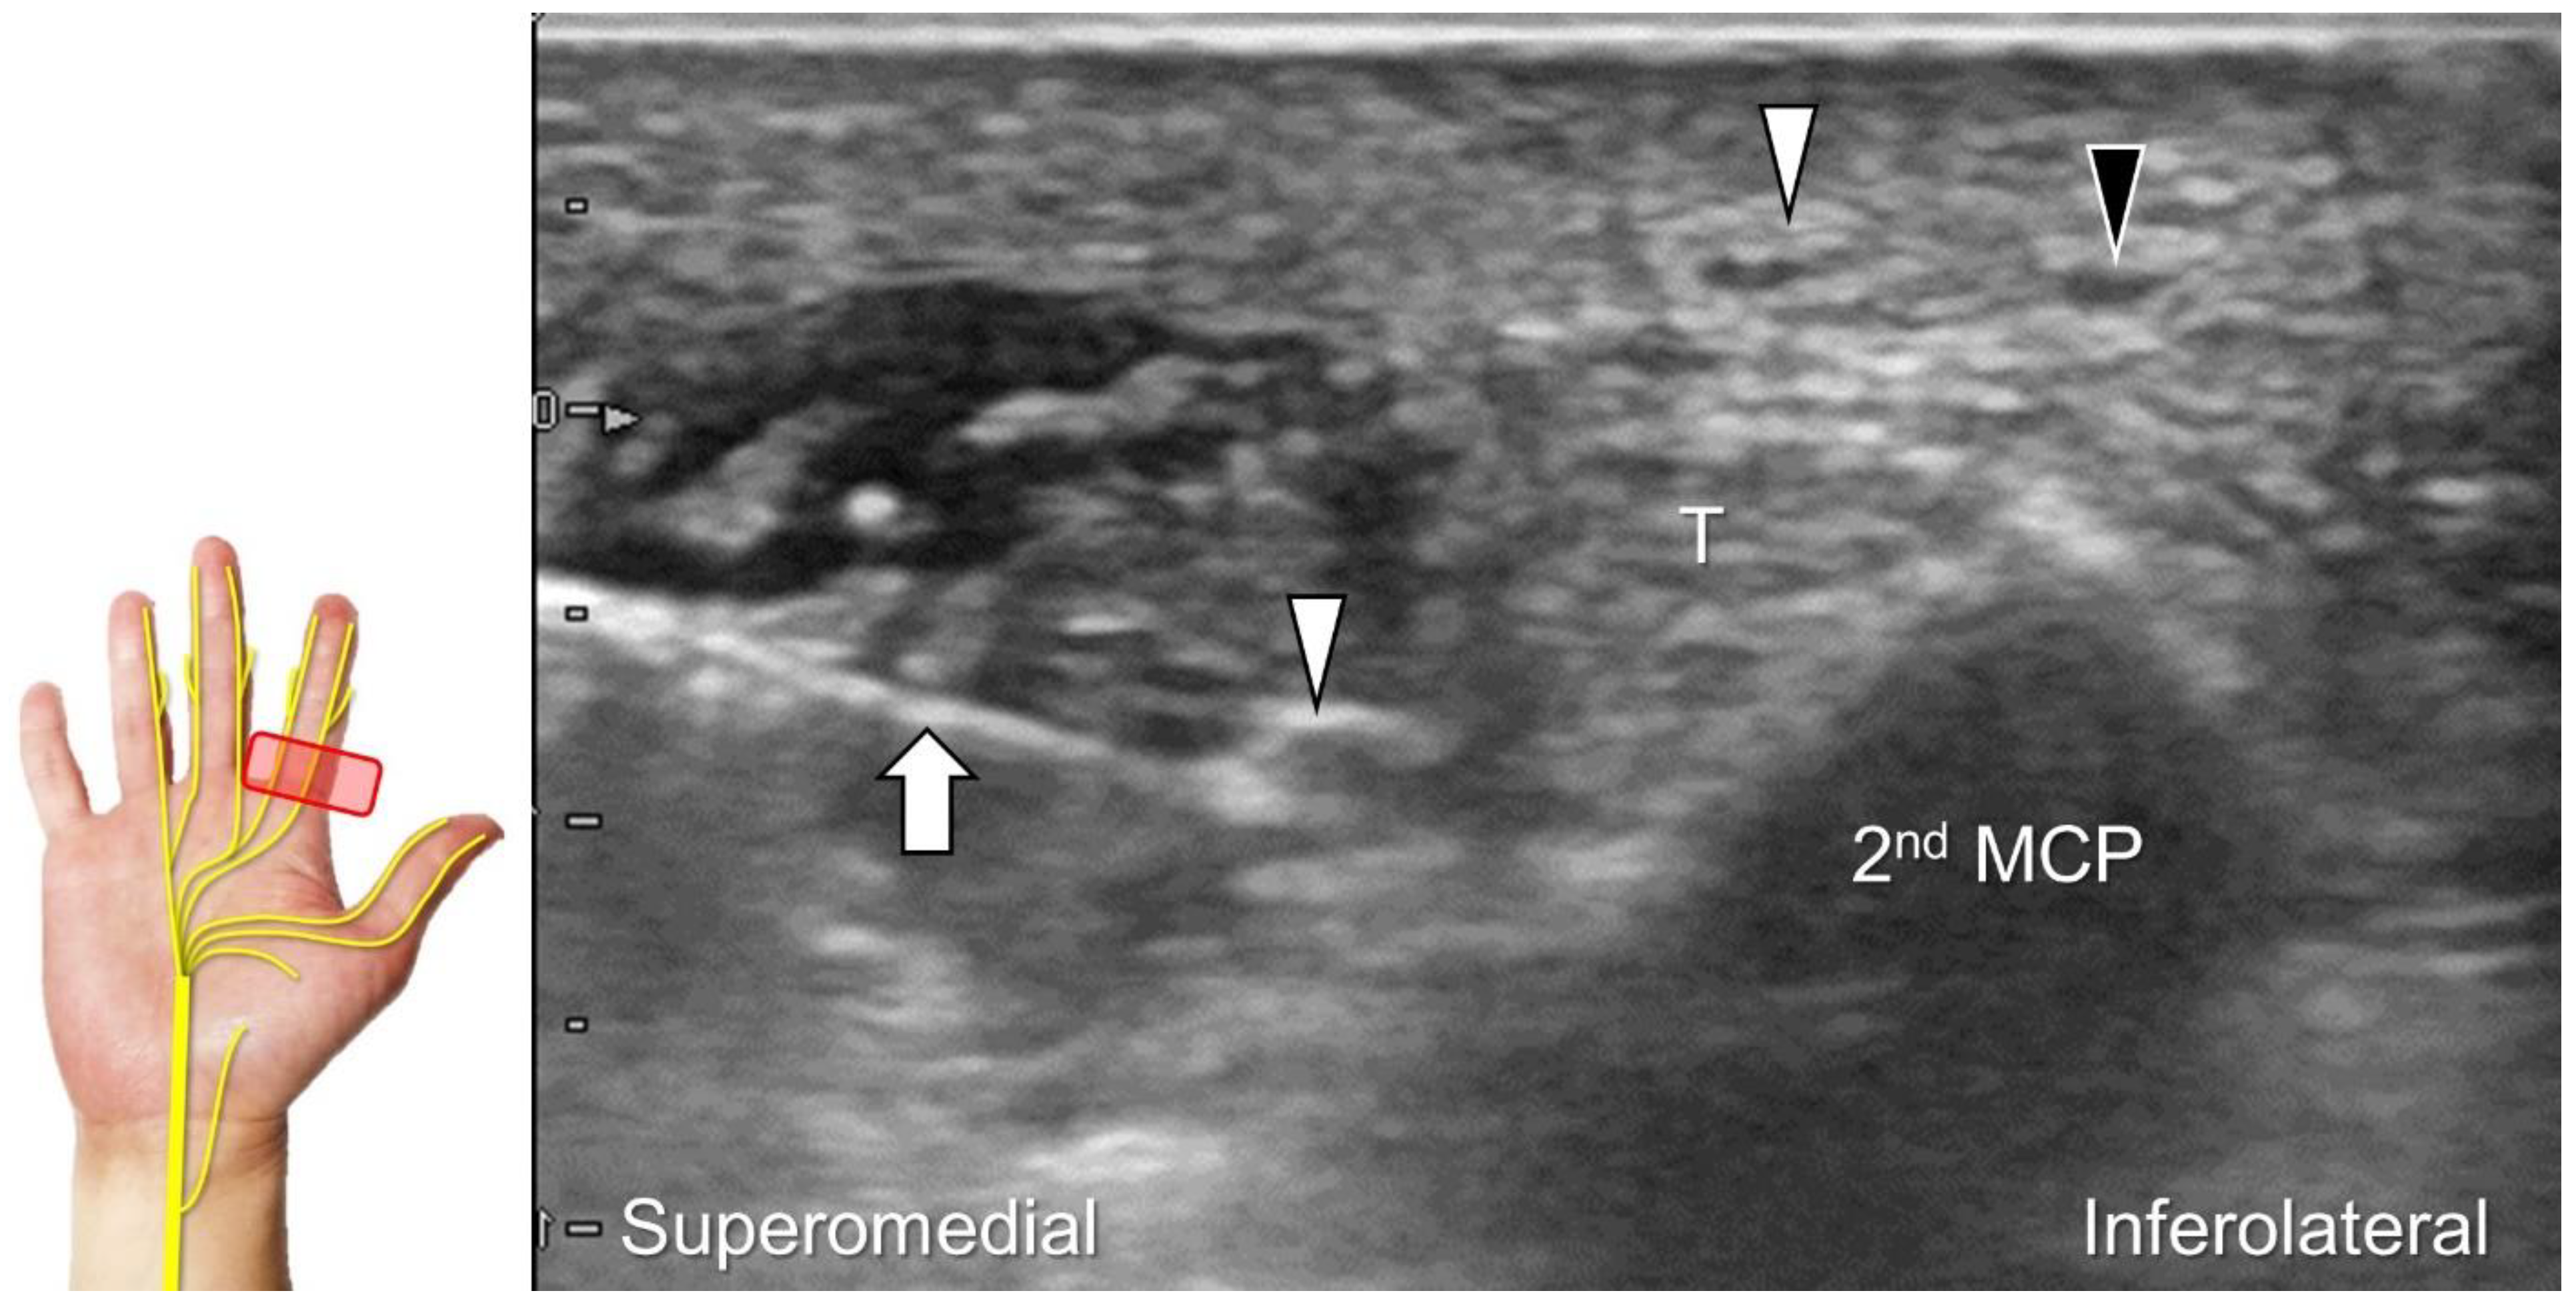

Figure 32. In-plane ulnar to radial approach is used for injecting the palmar common digital nerve in short-axis view. White arrowheads: palmar common digital nerve; black arrowhead: common palmar digital artery; arrow: needle; T: flexor tendons; 2nd MCP: second metacarpal.